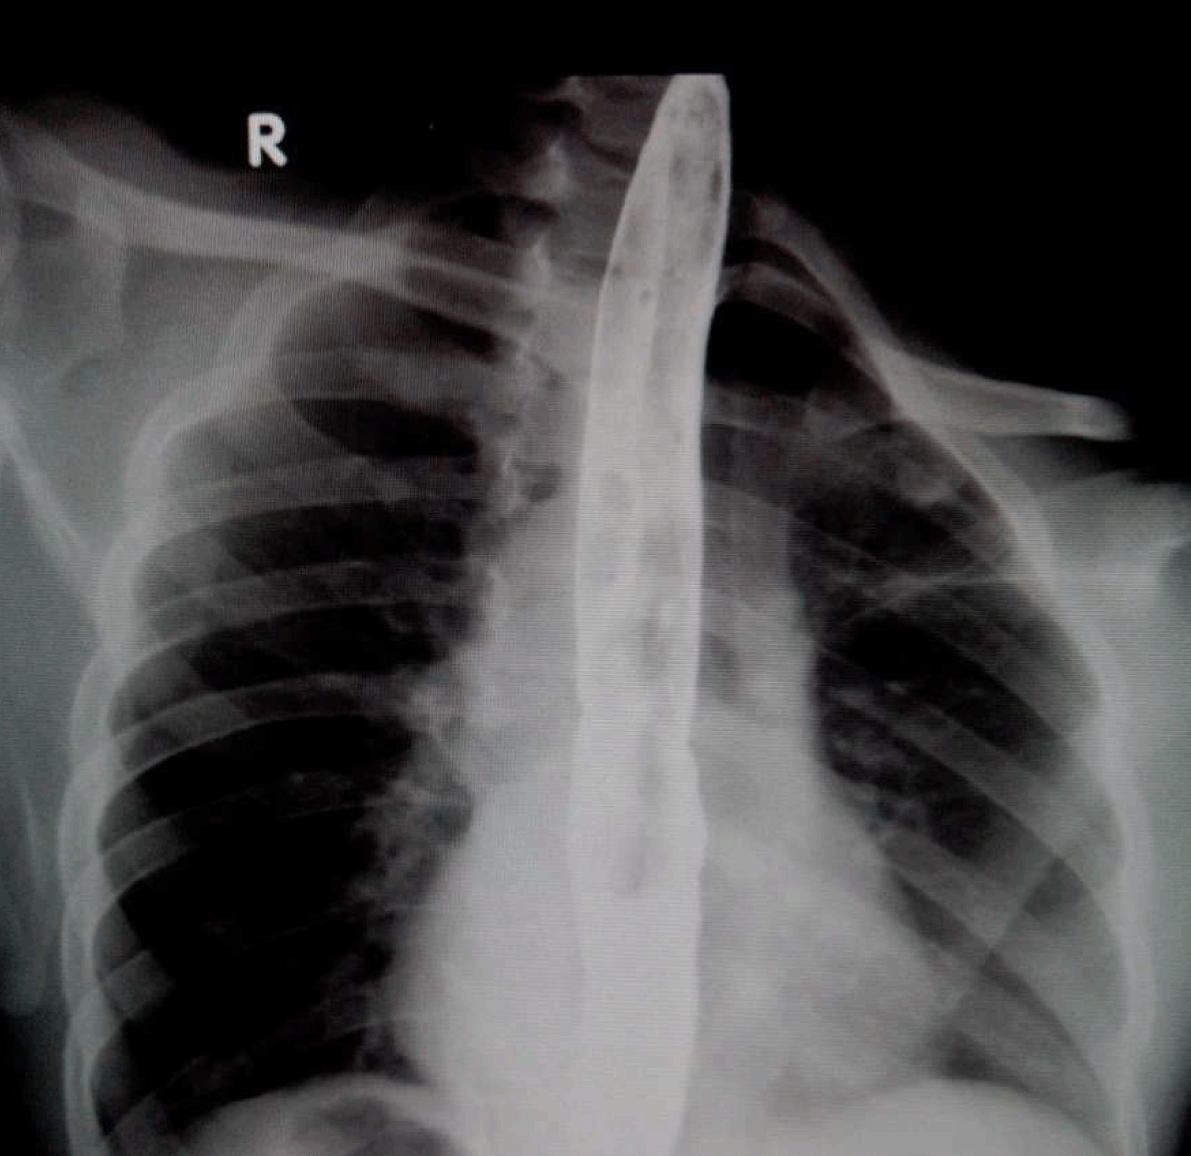

A 37-year-old male presented to our department with history of cough with expectoration immediately after taking food, especially liquids for last 13 years. He had two bouts of hemoptysis in the last 15 days which had made him seek medical attention. Clinically, chest on auscultation had crackles in right infra-scapular region. Chest X-ray revealed patchy opacities in the right lower zone paracardiac region. Computed tomography (CT) scan of thorax revealed consolidation in posterior segment of the right lower lobe with no evidence of lung sequestration or cyst. Upper gastrointestinal endoscopy showed a fistulous opening in the mid esophagus 32 cm from the incisor teeth. It did not show any evidence of malignancy, granulomatous disease or any other acquired basis for the fistula. Simultaneously, methylene blue was injected into the fistulous tract and bronchoscopy was done which was normal. Barium swallow showed fistulous communication between mid esophagus and right lower lobe bronchus at lower border of T7 with barium passing downward into the right lung (Figure 1).

Figure 1: Barium esophagogram showing esophagobronchial fistula between the middle third of the esophagus and the right lower bronchus with downward passage of barium (shown with arrow).